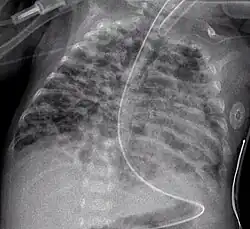

Diffuse shadowing

The differential for diffuse shadowing is very broad and can defeat even the most experienced radiologist. It is seldom possible to reach a diagnosis on the basis of the chest radiograph alone: high-resolution CT of the chest is usually required and sometimes a lung biopsy. The following features should be noted:

Pleural effusions may occur with cancer, sarcoid, connective tissue diseases and lymphangioleiomyomatosis. The presence of a pleural effusion argues against pneumocystis pneumonia.